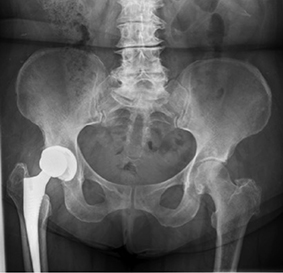

A 66-year-old woman, reported sudden functional inability to walk accompanied by snapping on limb mobilization 43 months after total right hip replacement (Corail, Pinnacle cup 48, ceramic head 32, +4 10° oblique PE oriented posteroinferiorly). Radiographic findings were consistent with PE dissociation with adequate acetabular abduction and anteversion, 41° and 28° respectively, as measured in plain X-rays (Figure 1) (Figure 2). During revision surgery, adequate component orientation was confirmed. The insert (+4 10° oblique) showed signs of wear and deformation in the posteroinferior elevated rim, (Figure 3). The oblique insert did not provide greater stability but caused impingement, so it was exchanged to a ceramic insert and a 32+5 head.

Figure 1. AP Pelvis view. Radiographic findings consistent with polyethylene dissociation. Eccentric position of the prosthetic head. Case 2

Figure 1